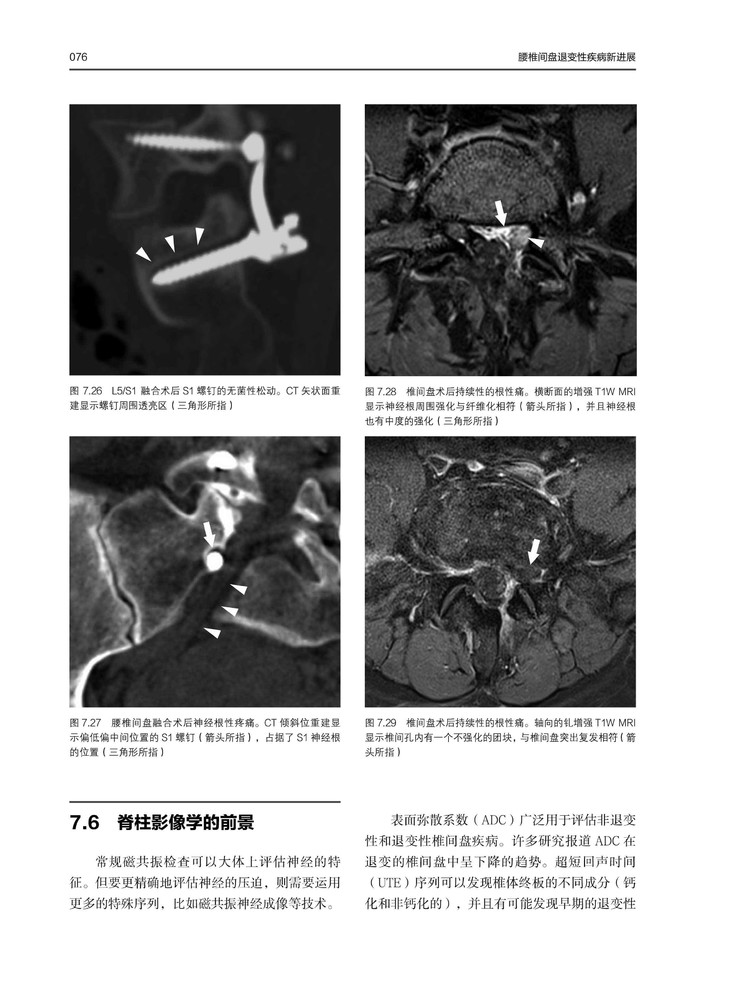

现在社会中腰椎间盘疾病患者逐年增加,本书重点介绍了腰椎间盘疾病的治疗方法,以及常见问题的解决办法。本书从物理病理学、遗传学和现代成像技术的理解等方面入手,对疾病的病因和治疗进行详细分析。同时,本书收集了大量病例,结合术图片中及术后影像学资料对病例进行分析,对临床医生工作具有参考价值。

在这本书中,脊柱领域的主要国际专家联合起来讨论了治疗腰椎间盘疾的主题、问题和方法。覆盖范围广泛,从目前从对物理病理学、遗传学和现代成像技术的理解,到各种微创性、非融合性和融合性手术技术。当接近病人并作出治疗决定时,需要仔细考虑最重要的方面。对保守治疗的作用进行了评估,并对手术技术及其适应症作了详细的描述。在总结部分,则是一些来自世界各地的顶尖专家都在反思他们在脊柱外科手术中所学到的经验教训。